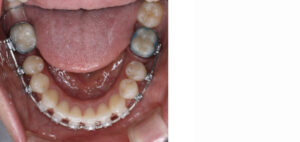

下顎左右の奥歯が失われた状態でしたが矯正治療でスペースを閉じて、上の歯は左右の小臼歯を抜歯して矯正用のアンカースクリューを併用して上の前歯を後ろに下げる治療を行いました。

結果、前歯の出っ張りが改善し自然に口を閉じられるようになり奥歯でしっかり噛める様になりました。(装置はハーフリンガル)

矯正治療中(下顎)